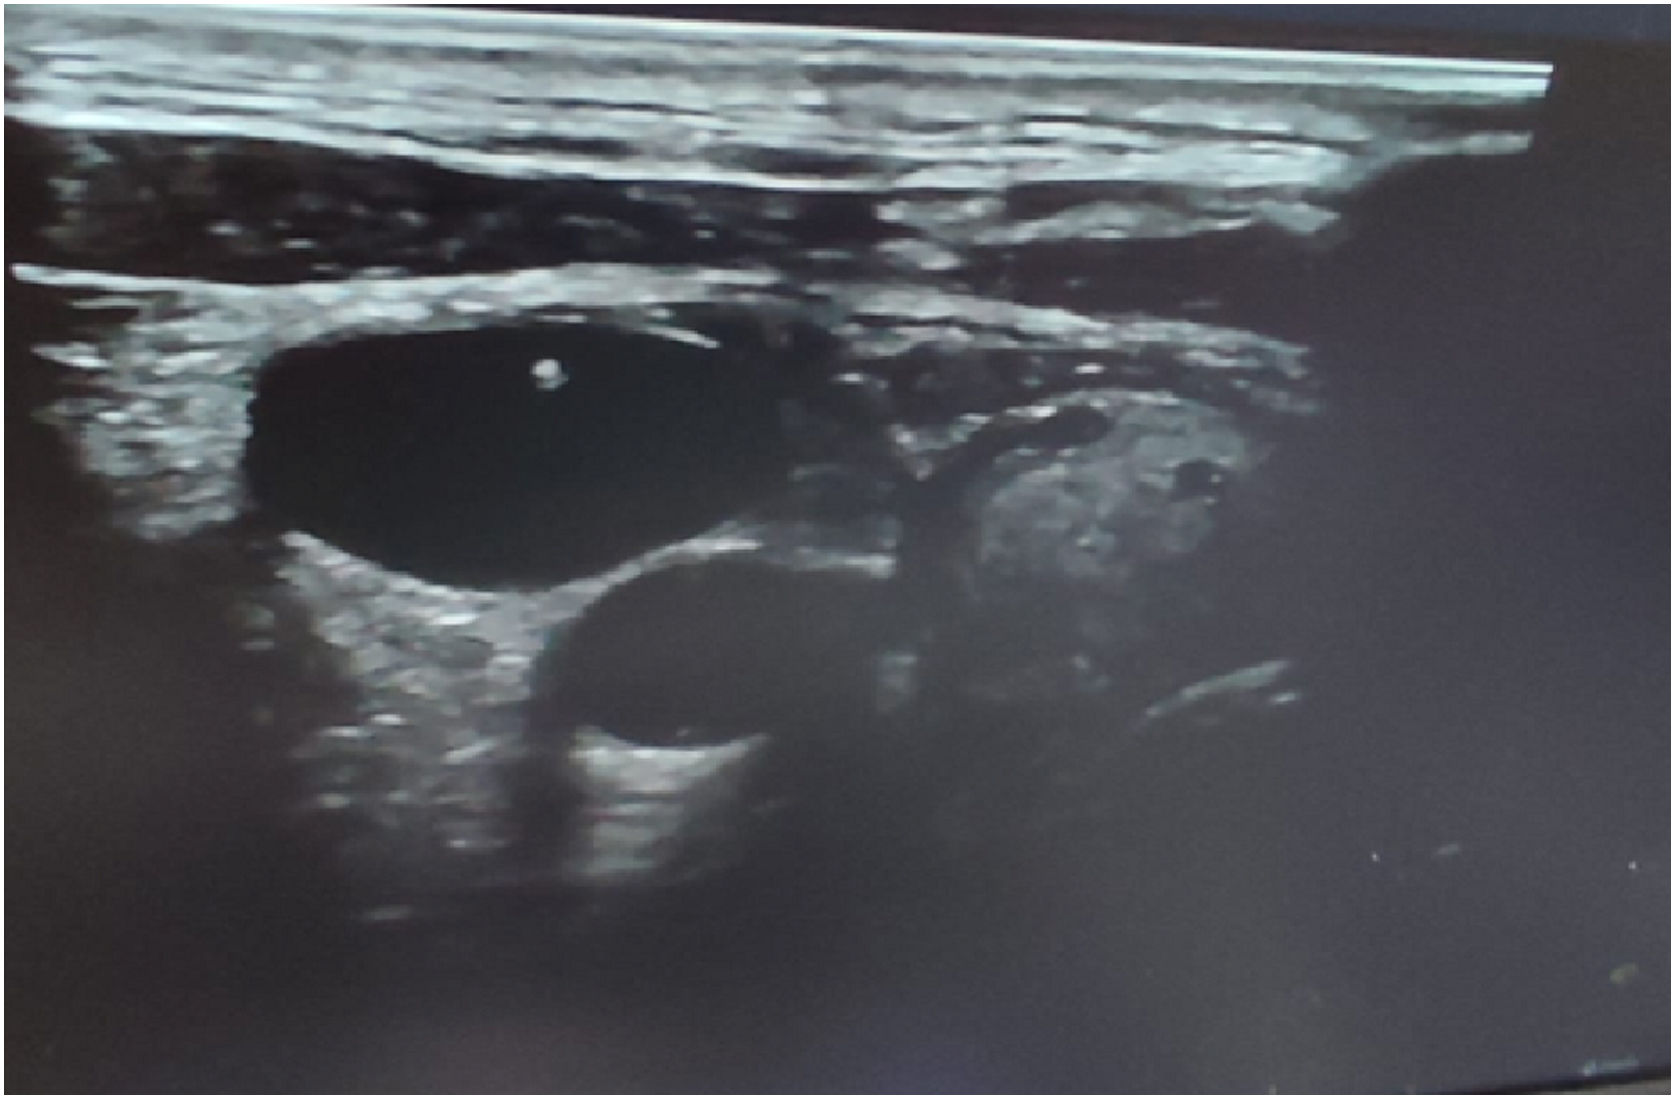

ResultsPatient ages ranged from 17 to 80 years with 56% being males. Urgent indications were found in around 22% without significant differences between groups. Regarding the time of performance, the ultrasound-guided method had slightly but significantly less time of performance (25.7 ± 4.3; range: 18−33) compared to the blind technique (26.9 ± 7.4; range: 15−45) (P-value < 0.001) with a higher but non-significant number of patients without complications (64% vs 52%; P-value = 0.2). Failure to insert the CVC into the IJV occurred in 12 patients (12%) with the blind technique and in eight patients (8%) with the ultrasound-guided technique (P-value = 0.04). Carotid artery puncture with neck hematoma occurred in only 8 (8%) patients with the blind technique (P-value = 0.04). Excess cost was consumed in only 36 patients (36%) in the blind technique group (P-value = 0.001).

ConclusionPoint-of-care ultrasonography bundle for CVC insertion is considered superior to, safer, and more cost-effective than the blind technique.